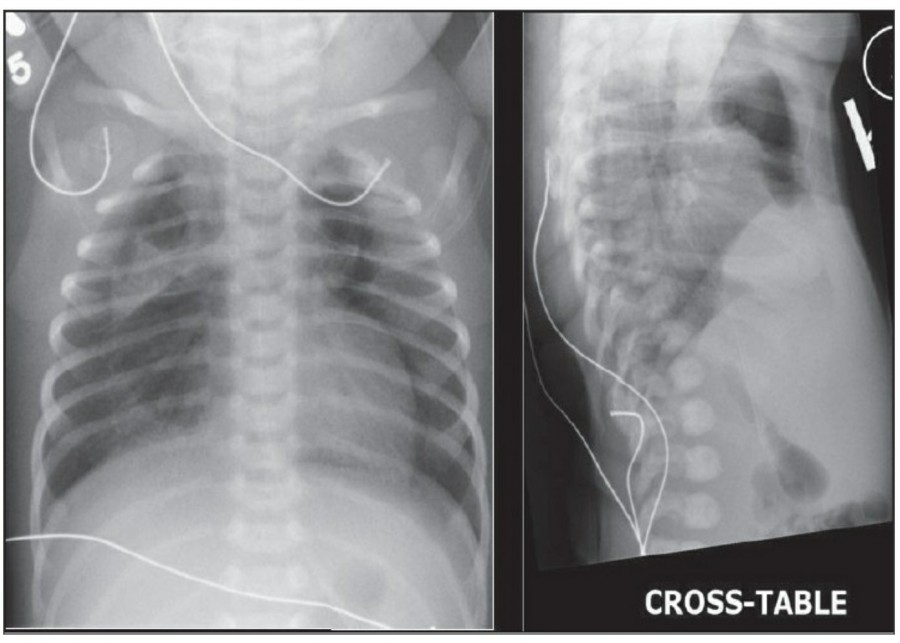

Temporary cardiac pacemaker는 cephalic vein이나 subclavian vien을 통해 right ventricl에 거치시킨다. AP, lateral chest X ray가 위치 확인을 위해 필요한다. Cardiac pacemaker의 tip은 심첨부에 위치해야 하며, pacemaker wire의 line이 꺾여 있어서는 안 된다. Lateral radiograph가 cardiac trabeculae 안에 묻혀 있는 tip을 확인하는데 도움이 된다. 제대로 거치된 게 맞다면 그 tip은 epicardial fat pad의 3, 4mm 안에 있어야 하며, 그 이상 넘어간다면 myocardium 천공 가능성이 있다. Coronary sinus 안에 들어갔을 경우 lateral radiograph 상에서 posterior 쪽에서 발견할 수 있다.